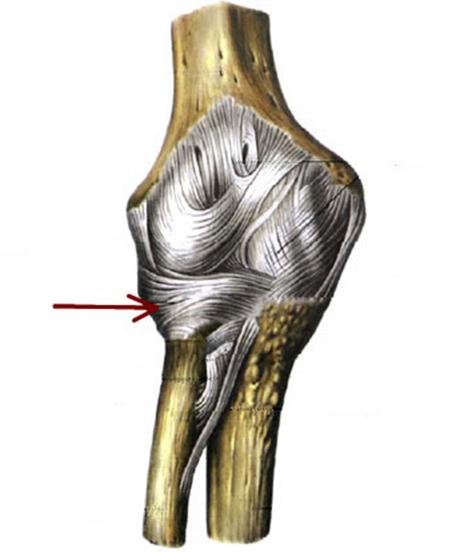

I:

S: Стрелка указывает на... плечевой кости.

-:tuberculum majus

+:tuberculum minus

-:epicondylus medialis

-:troсhlea

-:capitulum